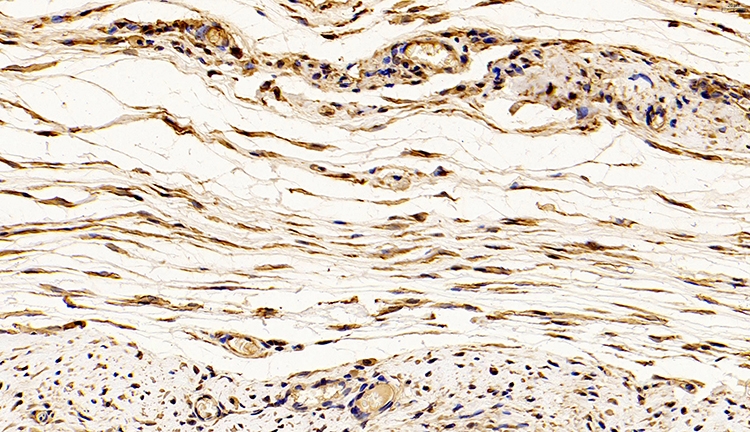

免疫荧光通过抗体与示踪物质结合,利用抗原-抗体结合反应,进而对抗原所在的细胞或组织进行定性或定量。

由于荧光素所发的荧光可在荧光显微镜下检出,荧光素受激发光的照射而发出明亮的荧光,可以看见荧光所在的细胞或组织,利用定量技术测定含量,从而可对抗原进行细胞定性和定位分析。

免疫荧光实验可以快速直观的显示所检测蛋白的细胞定位。

细胞成像:通过将荧光标记的抗体与目标分子结合,免疫荧光实验能够在细胞水平上可视化和观察目标分子的位置和分布情况,帮助研究人员了解细胞内分子的功能和相互作用。